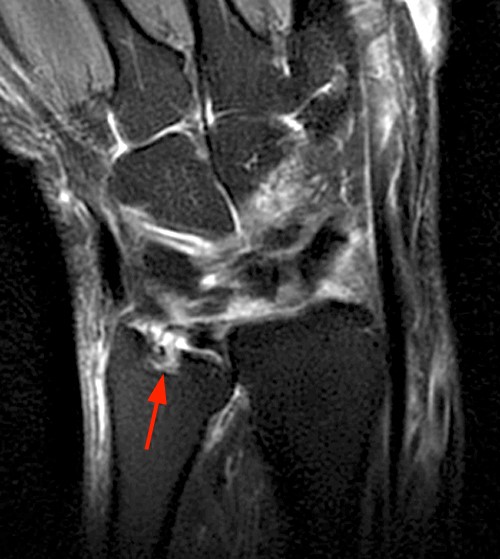

From mrimusculoskeletalsection.blogspot.com

MRI MusculoSkeletal Section Rheumatoid arthritis of the wrist. Arthritis In Ulnar Side Of Wrist The objectives of this article are to provide an overview of the most common problems that are encountered in the diagnosis. This causes pain with turning the hand palm up or palm down. If you’re experiencing wrist pain, you may be suffering from a type of arthritis such as rheumatoid arthritis or osteoarthritis. The wrist bones in a normal wrist. Arthritis In Ulnar Side Of Wrist.